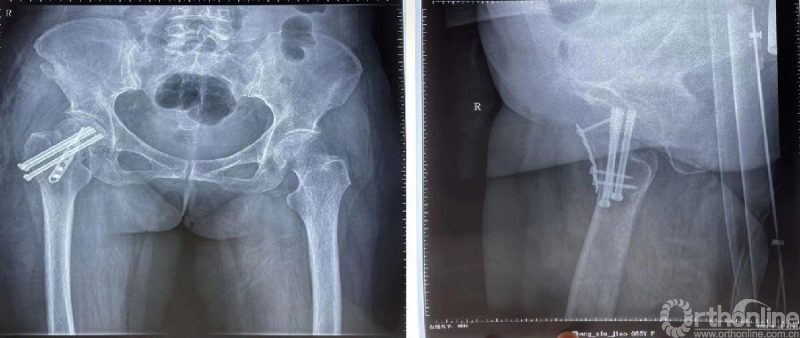

影像学资料

诊断:1、股骨颈骨折(Garden III);2、帕金森病

初次治疗:闭合复位空心螺钉内固定

术后影像资料(2022.3.2)

术后2个月(2022.5.27)